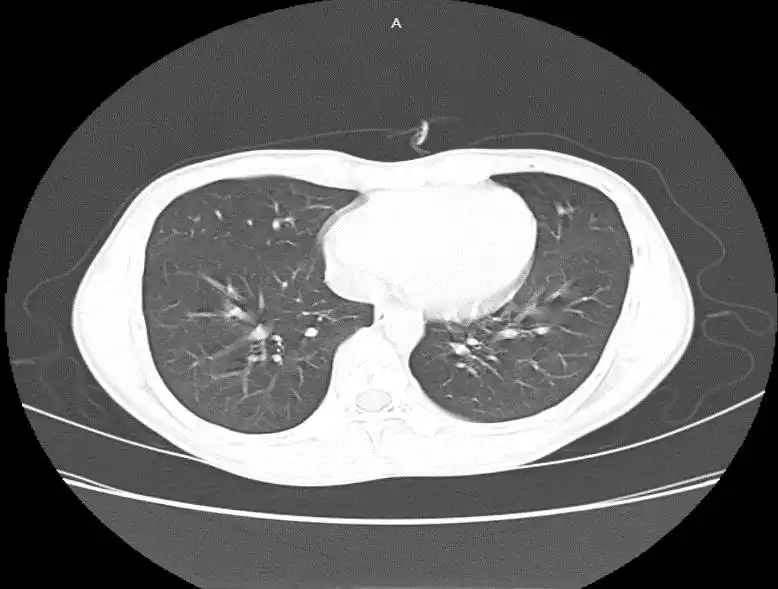

Đến ngày điều trị thứ 11, không còn ghi nhận khí thoát ra qua ống dẫn lưu. Hình ảnh X-quang và cắt lớp vi tính (CLVT) ngực xác nhận phổi nở hoàn toàn, không còn hình ảnh tràn khí màng phổi và không phát hiện kén khí tồn lưu. Căn cứ vào diễn biến lâm sàng và cận lâm sàng ổn định, ống dẫn lưu được rút an toàn. Người bệnh được xuất viện sau 12 ngày điều trị trong tình trạng ổn định.

Cắt lớp vi tính (CLVT) ngực trước thời điểm rút dẫn lưu và X-quang ngực sau rút dẫn lưu cho thấy phổi nở tốt, không còn hình ảnh tràn khí trong khoang màng phổi. |